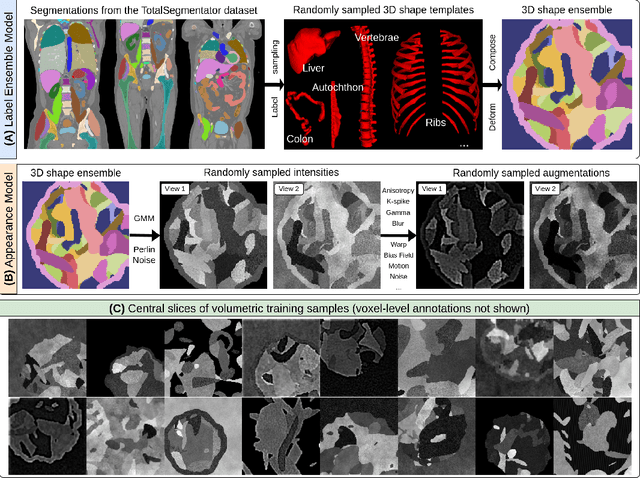

Abstract:Current volumetric biomedical foundation models struggle to generalize as public 3D datasets are small and do not cover the broad diversity of medical procedures, conditions, anatomical regions, and imaging protocols. We address this by creating a representation learning method that instead anticipates strong domain shifts at training time itself. We first propose a data engine that synthesizes highly variable training samples that enable generalization to new biomedical contexts. To then train a single 3D network for any voxel-level task, we develop a contrastive learning method that pretrains the network to be stable against nuisance imaging variation simulated by the data engine, a key inductive bias for generalization. This network's features can be used as robust representations of input images for downstream tasks and its weights provide a strong, dataset-agnostic initialization for finetuning on new datasets. As a result, we set new standards across both multimodality registration and few-shot segmentation, a first for any 3D biomedical vision model, all without (pre-)training on any existing dataset of real images.